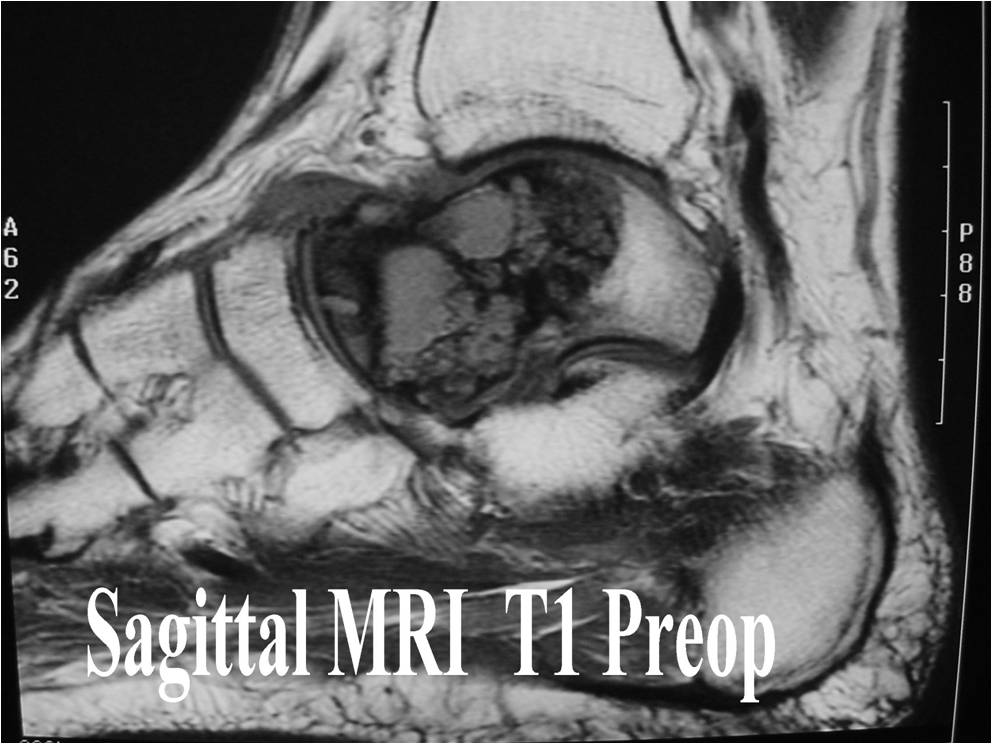

General Information Enchondroma is a benign indolent intramedullary hyaline cartilage neoplasm Accounts for 10% of all benign osseous tumors Limited growth, most lesions are less than 5 cm in maximal dimension Bones grow from a cartilaginous growth plate that...